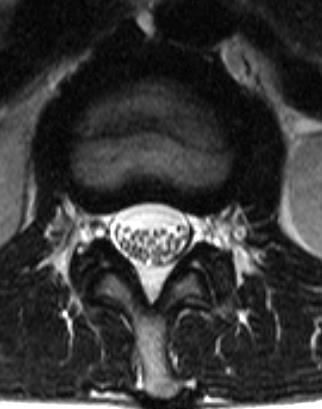

МРТ (аксиальная томограмма)